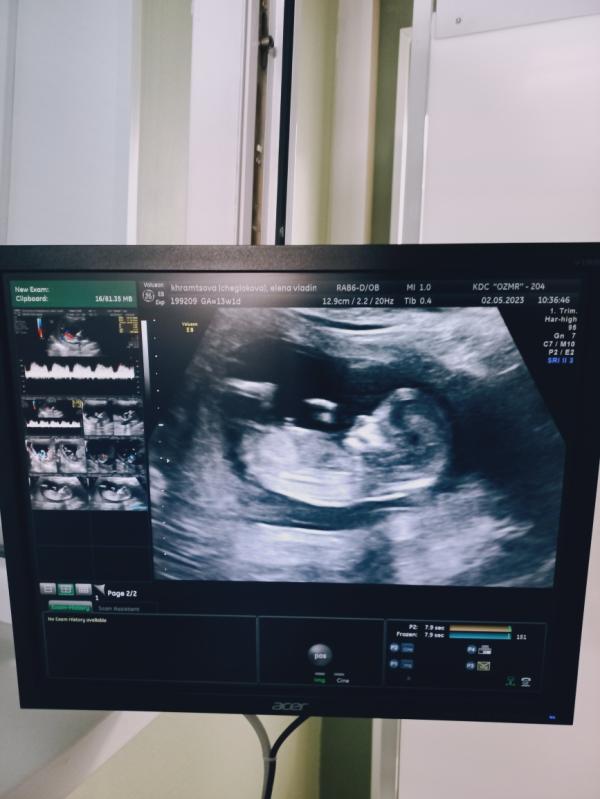

Пройден первый скрининг( Флотская, 52), сколько же было страхов... 🤯 Как никогда, ни в одну беременность я так не переживала. Видимо все таки "горе от ума", слишком много читала статей, комментариев, зачастую лишних и ненужных... Слава Богу все показатели роста и развития в норме, все риски низкие, несмотря на мои 37 лет))

Но всё же напугало переднее прикрепление плаценты, предсказывают большие риски недостаточности плаценты, ее отслоения и тд, так ли это опасно на самом деле ?